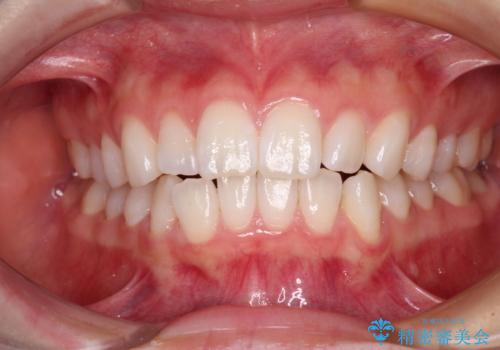

- 前歯の出っ歯と口元の閉じにくさを気にして来院された患者様です。

口元を積極的に引っ込めるために、上下左右の小臼歯4本を抜歯することとしました。

4本の歯を抜歯したことで、飛び出していた口元が引っ込み、横顔が大きく改善されました。